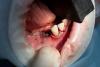

Pavel Y. Опубликовано 2 июня, 2013 Поделиться Опубликовано 2 июня, 2013 (изменено) Добрый вечер уважаемые коллеги. Вот наконец-то решил стать участником уважаемого форума. Как говориться, с пустыми руками неприлично... Работа двухлетней давности, многими методиками на том момент еще не владел. Поэтому критику ожидаю, но все же. Ведь это наше знакомство На нижней челюсти по данным КТ ширина гребня на нижней челюсти варьировала от 4-6 мм. Высота удовлетворительная. Принято решение провести имплантацию в позицию 34-36, 44-46. Удаление 37 зуба. Забор аутокости (стружка) с помощью "костного скребка" в третьем сегменте. Стабилизация мембраной Био Гайд Укладывается стружка:На тот момент я знал, что стружка под мембраной жить не сможет и, поэтому, я применил "сандвич" технику с Био осс (мелкий). Фиксация мембраны на пины:Многие скажут, что третья пина не нужна, но она так хорошо встала)))) Та же манипуляция проводится в четвертом сегменте: Ушивание раны. Через 2 недели снятие швов: Через 5 недель: До/После На сегодняшний день, пациентка отпротезирована временными реставрациями. С левой стороны потребовалась пластика мягких тканей, с правой второй этап проводился классически. Я понимаю, многим такой подход неприемлем и сейчас бы я применил уже другую тактику, но такая работа проведена и результат стабилен.Спасибо за внимание! Изменено 2 июня, 2013 пользователем Pavel Y. 1 Ссылка на комментарий